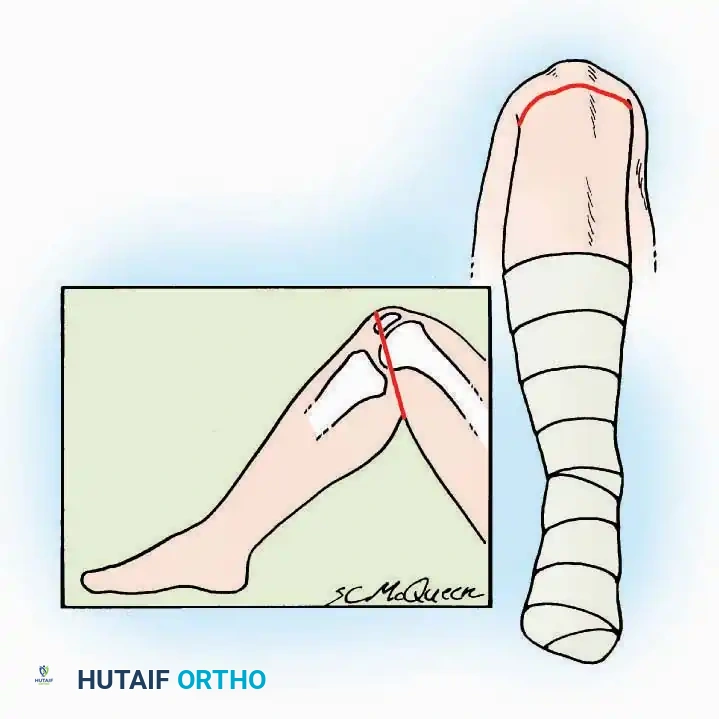

Postoperative Protocol Considerations

Regardless of the approach utilized, meticulous layered closure is mandatory to eliminate dead space and prevent hematoma. The extensor retinaculum should be repaired when possible to prevent tendon bowstringing. Postoperatively, the limb must be immobilized in a bulky, well-padded posterior splint in a neutral position, accompanied by strict elevation to minimize edema and protect the vascularity of the surgical flaps. Suture removal is typically delayed until 14-21 days in foot and ankle surgery due to the tenuous nature of distal extremity perfusion.